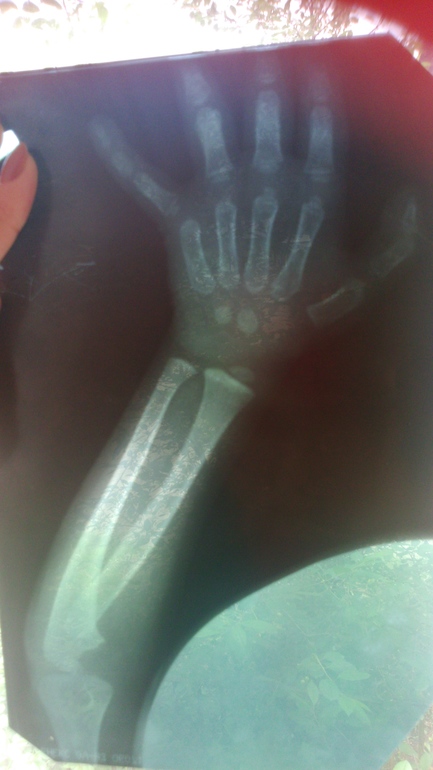

Здравствуйте, в воскресенье вечером ребенок упал на руку на камни, после очень кричал долго, не давал трогать руку. Сделали рентген, врач сказал ничего не вижу, замотали просто бинтом ничего не сказали отпустили, вроде как просто ушиб, пройдет. Синяков, кровоподтеков,шишек, припухлости нет,все чисто. Но он рукой почти не шевелит,слегка может согнуть в локте и пошевелить пальчиками. Кисть почти не двигается, в руку взять ничего не может,пальцы в кулак не сгибаются,предметы в руке не держаться. При этом плачет говорит больно и убирает руку. При попытке согнуть в локте до конца тоже плачет. Очень переживаю, может врачи что то упустили, у нас в деревне плохой рентген, не всегда видят переломы, трещины, заболевания легких, люди ездят в город. Боюсь не упустить момент, чтоб руку можно было полностью восстановить. Подскажите что нам делать, может ли это быть просто ушиб или врачи ошиблись???снимок есть фото не очень получилось, может что то увидите